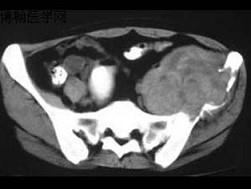

问题 患者,男性,33岁,近2年来感左髂部疼痛,活动后加重,3周前由于剧烈运动后左下肢活动不能,查体左髋压痛明显,皮肤稍显红肿,请结合所提供的图像,选择最佳选项 ( )

选项 A、软骨瘤 B、软骨肉瘤 C、骨巨细胞瘤 D、骨囊肿 E、动脉瘤样骨囊肿

答案 E